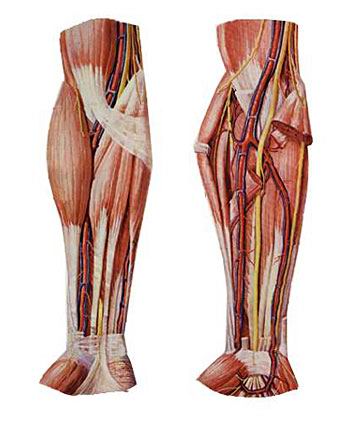

(3)坐骨神经

坐骨神经是全身最大的神经。于梨状肌下缘出骨盆,行于臀大肌深面,经坐骨结节与大转子连线的中点,下行至腘窝,分为胫神经和腓总神经。坐骨神经本干布于髋关节和股肌后群。

1)胫神经

沿腘窝中线,经小腿后群肌深浅两层间下降,于内踝后方至足底分为足底内侧神经和足底外侧神经。

胫神经肌支支配小腿后群肌、足底肌。皮支布于膝关节、小腿后面皮肤、足底皮肤。胫神经损伤后表现为足“勾状外翻”。

2)腓总神经

沿腘窝上外侧缘向外,绕腓骨胫,分为腓浅、腓深神经。腓浅神经肌支支配小腿外侧群肌,腓深神经肌支支配小腿前群肌。腓总神经损伤后表现为足下垂伴内翻(即“马蹄内翻”)。